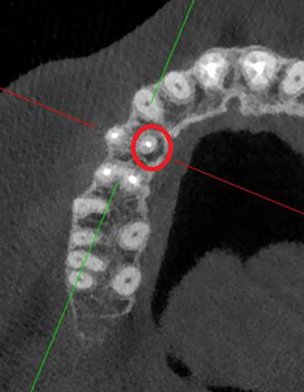

Проблема: У пациента жалобы на боли при накусывании и дискомфорт во время жевания. Ранее обращался в другие клиники, где было рекомендовано удаление зуба ввиду невозможности его перелечивания.

Лечение: Проведено перелечивание корневых каналов под микроскопом с удалением ранее внесённых материалов, тщательной механической и медикаментозной обработкой каналов и их последующей герметичной обтурацией. После лечения каналов выполнено восстановление коронковой части зуба.